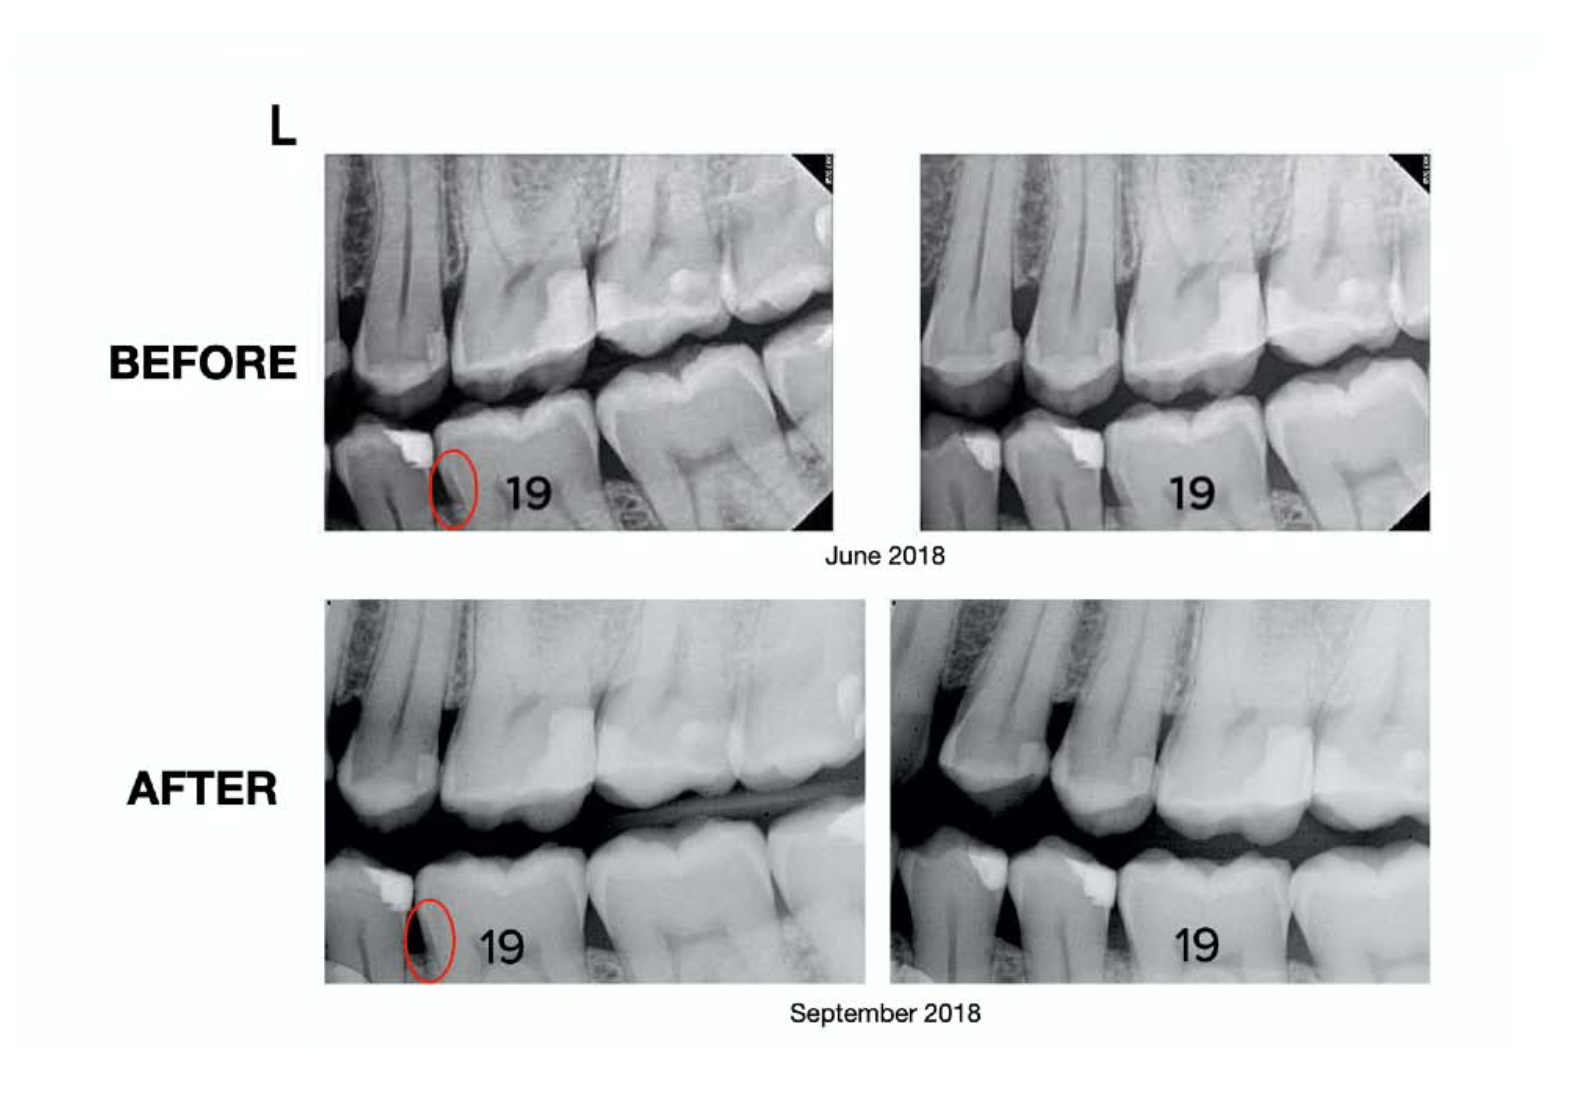

He took new X-rays. He examined my teeth carefully. Then he looked up and said something I will never forget: “I don’t see any cavities. Just keep up your good dental habits.” 2 I was stunned. No cavities. Not a single one. Every cavity I had been diagnosed with was gone. Still, I wanted absolute certainty. So I sent my before-and-after X-rays to a second dentist for an independent opinion, who said that the second newer set of x-rays didn’t show the cavities of the first one. I even showed the before and after x-rays to a third dentist who said, “There is definite remineralization in these second x-rays” The protocol had worked! Here’s the before and after X-ray’s for you to see for yourself.

Before & After X-rays

Your teeth can heal! Cavities can remineralize and I am living proof of that.